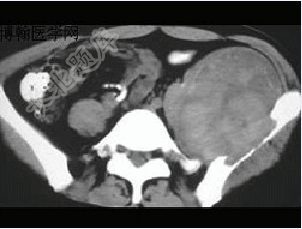

- 单项选择题患者,男性,33岁,近2年来感左髂部疼痛,活动后加重,3周前由于剧烈运动后左下肢活动不能,查体左髋压痛明显皮肤稍显红肿,请结合所提供的图像,选择最佳选项( )

A、骨囊肿

B、软骨瘤

C、骨巨细胞瘤

D、软骨肉瘤

E、动脉瘤样骨囊肿